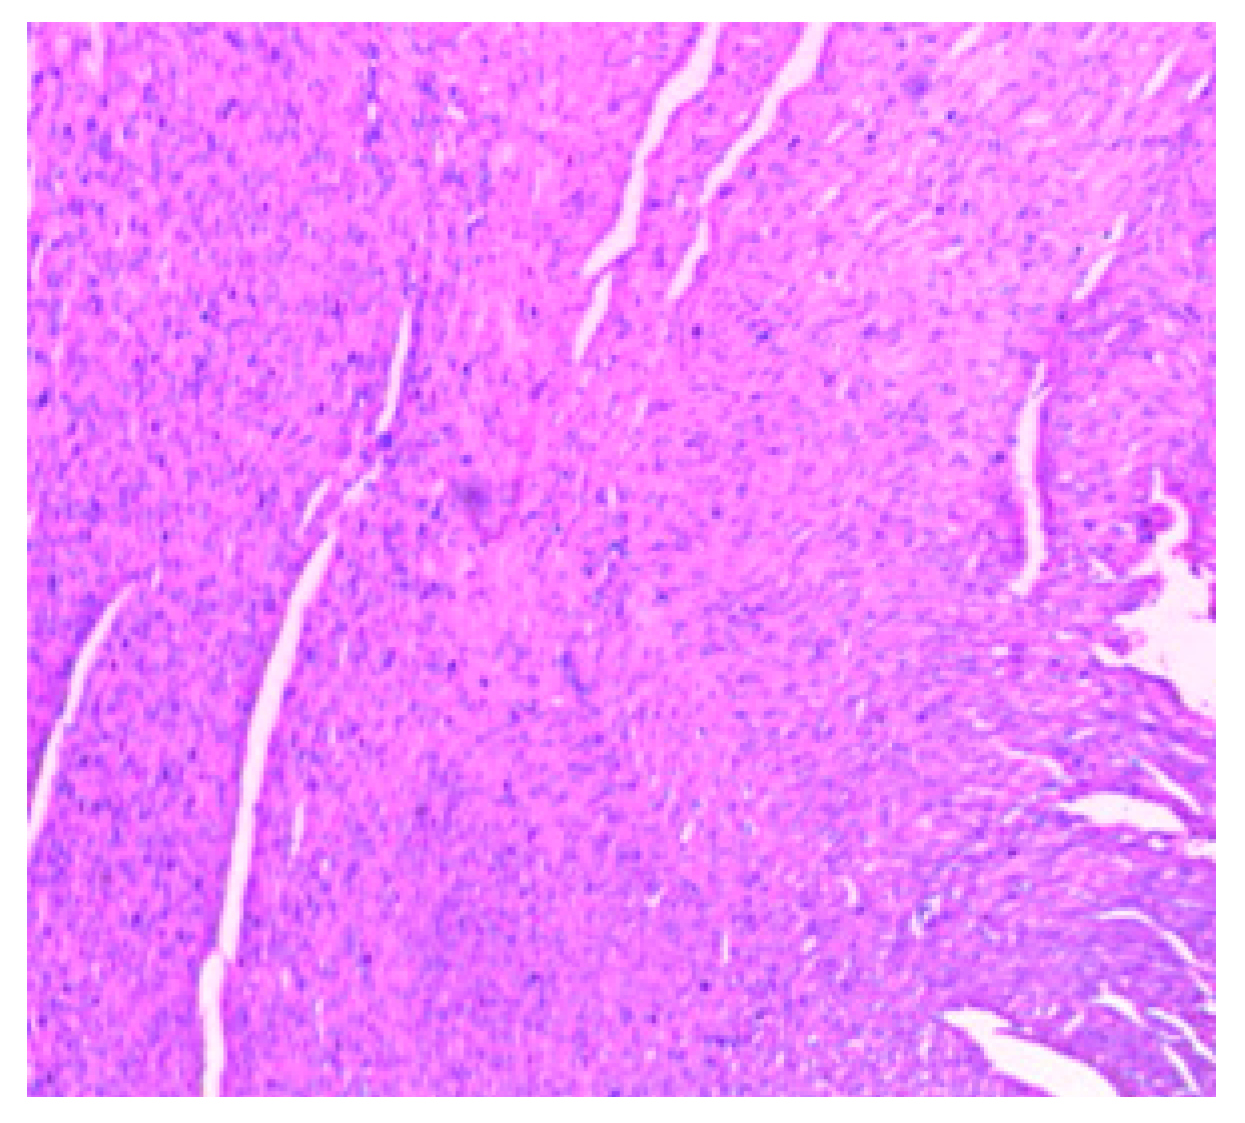

The histology of the hearts of the rat models examined is shown in Figure 13, Figure 14, Figure 15, Figure 16 and Figure 17. Gestation had no histological changes in the cardiac tissues (Figure 14 and Figure 15), while clay beverage consumption during both early and late gestation caused inflammation (Figure 16) and necrosis (Figure 17) of cardiac tissues. We deduce that the functional integrity of the cardiovascular system is at risk during gestation if clay beverage is part of nonfood substances frequently consumed.

Figure 16.

Histopathologic slide of the heart muscle of rats administered clay beverage during early gestation stage showing mild inflammation.

Figure 17.

Histopathologic slide of the heart muscle of rats administered clay beverage during late gestation stage showing inflammation and necrosis.